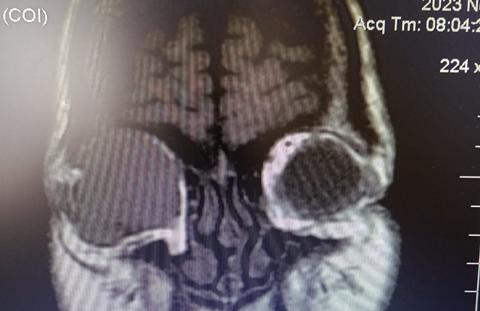

Se indica realización de TAC de órbita. Se realiza interconsulta con el Servicio de cabeza y cuello que decide cirugía de exenteración de contenido orbitario y envía de muestra a anatomía patológica.

La Tac de órbita informa tumoración en región orbitaria derecha. En tanto, los resultados del informe anatomopatológico indican:

• Tomografía de cerebro: informa enucleación ocular derecha, resto dentro de los parámetros normales.